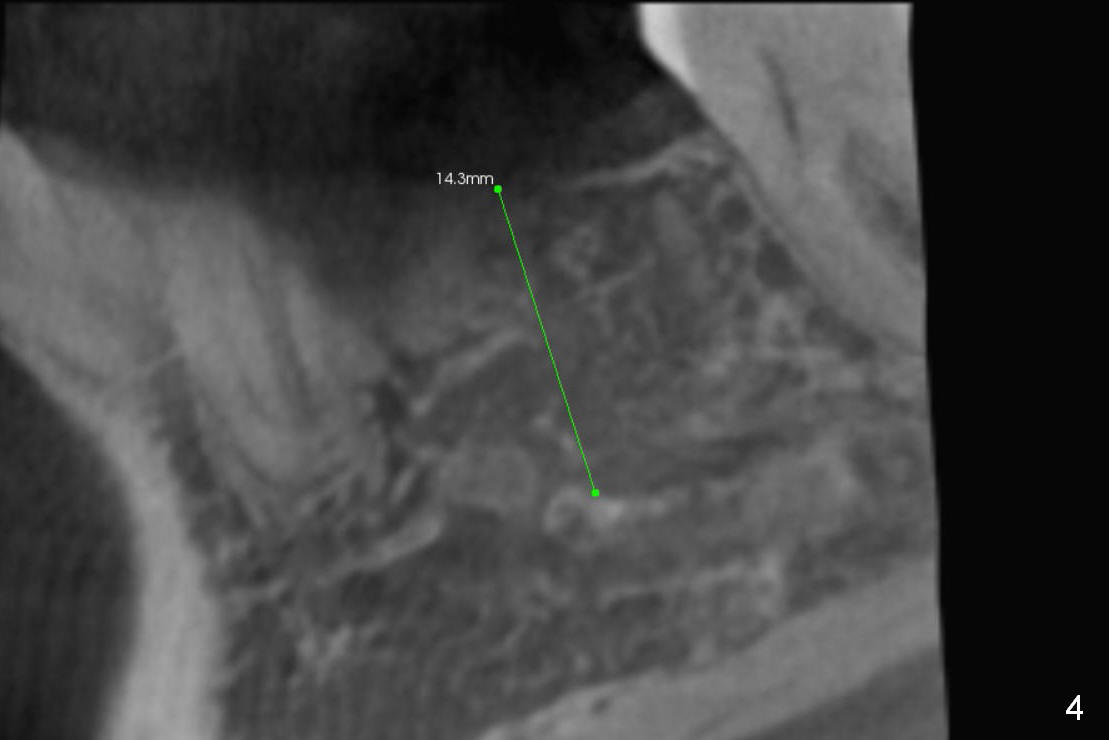

A 44-year-old black lady is a typical dental phobic. She has lost #19 for years with history of traumatic extraction. The ridge is atrophic (Fig.1). She is not comfortable with intraoral X-ray. So CBCT is taken. The coronal section shows that the bone density is low in the coronal ridge (Fig.2 arrowheads). It is difficult to determine the buccolingual width at crest; probably a 5.9x10 mm implant is appropriate (Fig.3). The most useful information from CT is height determination for the implant (Fig.4). The initial osteotomy depth is 10 mm (Fig.5); there is a large safety margin. There is a 2 mm clearance when a 4.5x12 mm implant is placed (Fig.6). Incision is sutured; a 8x4 (3) mm healing abutment is placed (Fig.7 arrowhead), followed by application of perio dressing. The latter remains stable 13 days postop thanks to the holding effect of the healing abutment (Fig.8 H). The wound has apparently healed when the dressing is removed (Fig.9). It appears that the edentulous space is extremely wide. The 4.5 mm implant may not sustain masticatory force. Limited orthodontic treatment appears to be necessary, using the implant as an anchorage to move the neighboring teeth (Fig.10 arrows). In fact the orthodontic treatment is not rendered. A crown is cemented 14 months postop. The cortical bone is thickened around the implant 15 months post cementation (Fig.11).